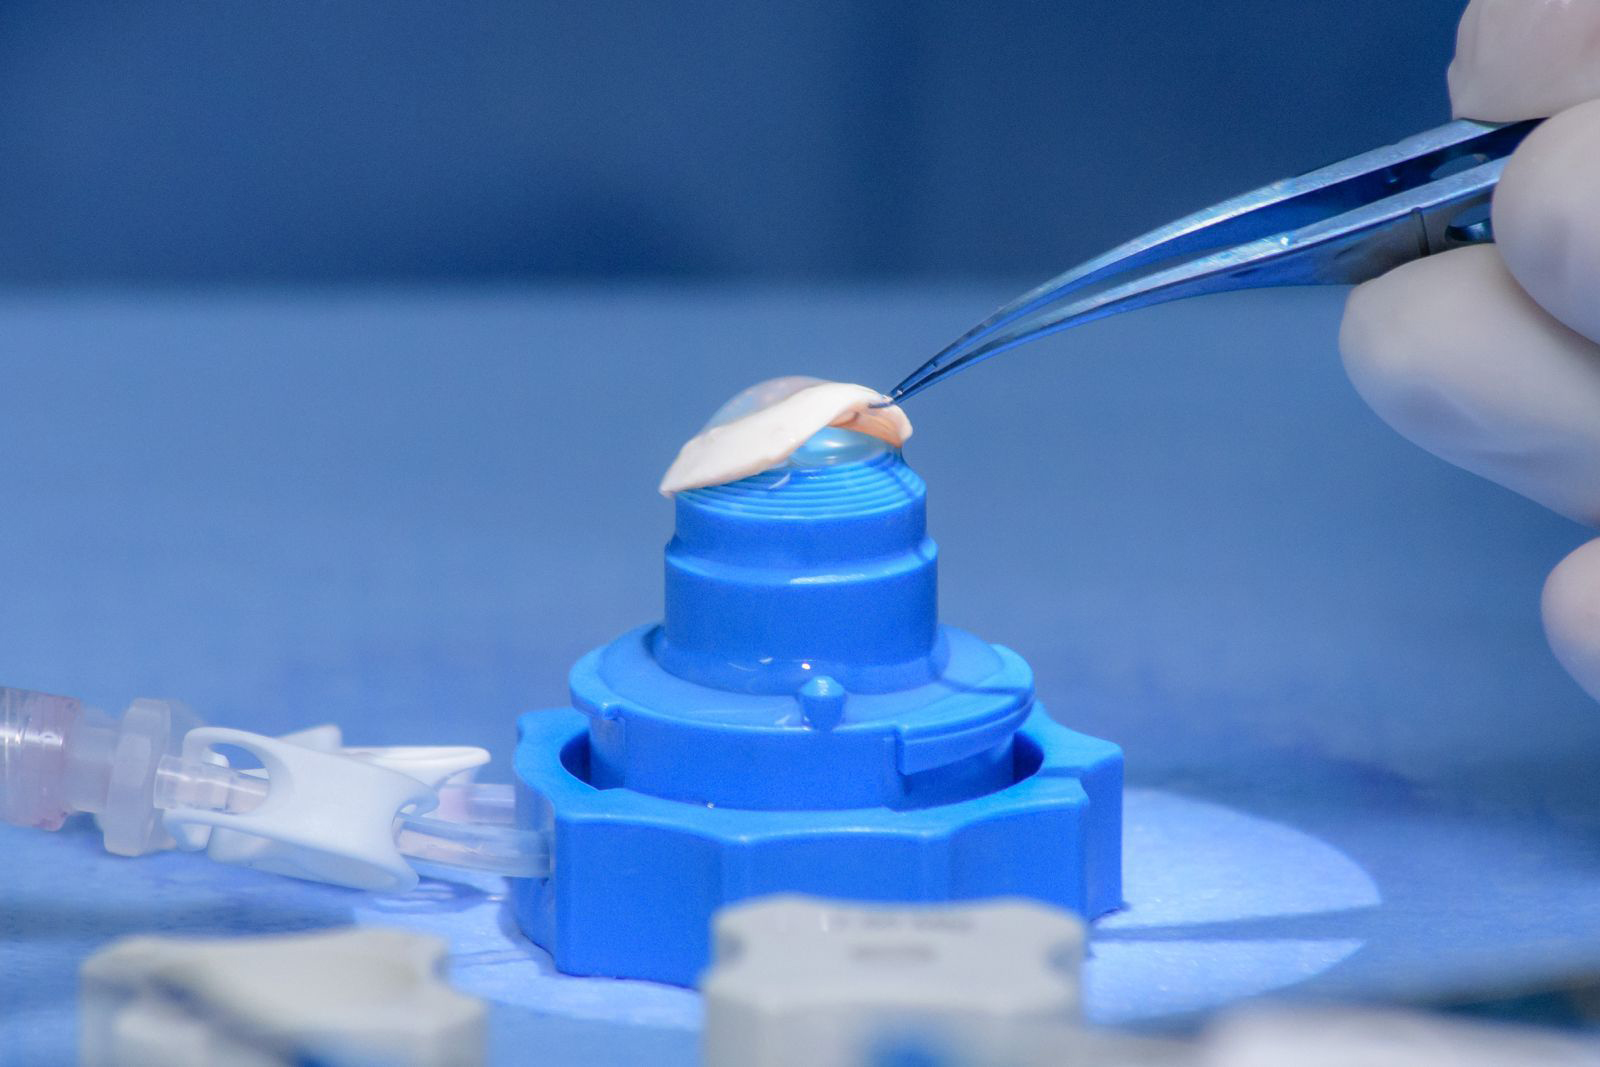

As cirurgias corneanas englobam diversos procedimentos modernos voltados ao tratamento de doenças e alterações da córnea, como ceratocone, cicatrizes, distrofias ou afinamentos. Entre as técnicas disponíveis estão os transplantes de córnea (lamelares e penetrante), o implante de anel intraestromal e o crosslinking corneano, que ajudam a recuperar a visão, fortalecer a córnea e melhorar a qualidade de vida do paciente.